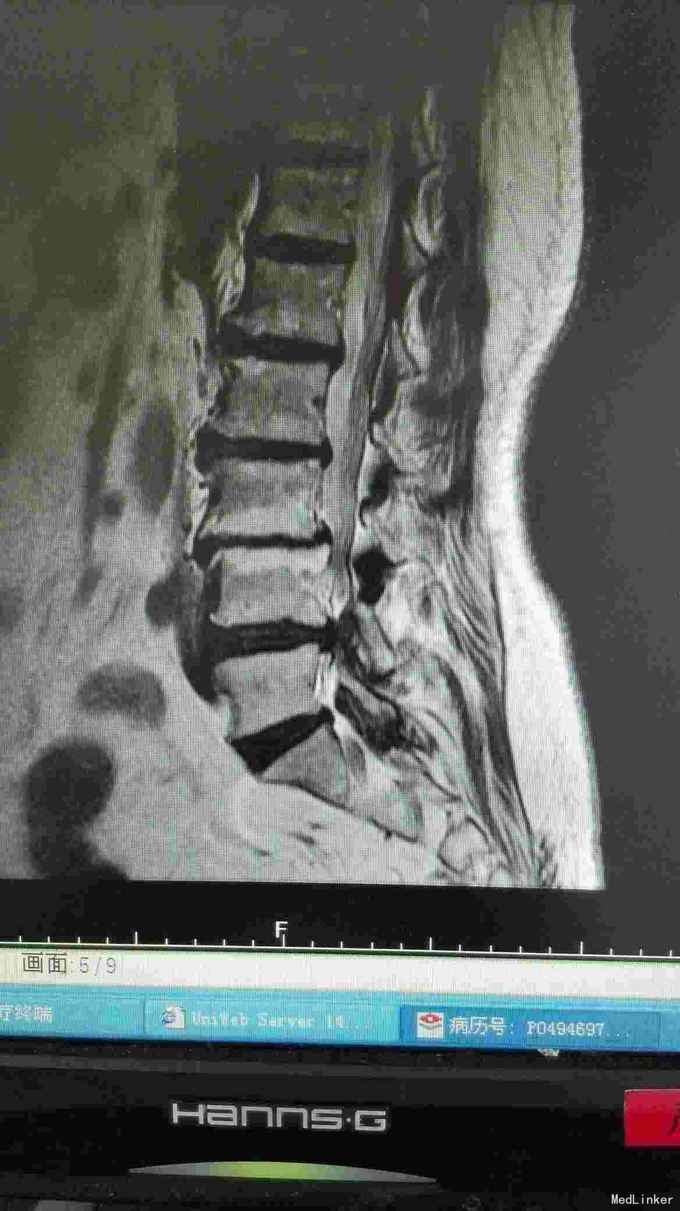

患者腰部疼痛伴右下肢疼痛麻木2年,间隙性跛行。

腰椎影像检查提示椎间盘突出,椎管狭窄,退变侧弯。

诊断腰椎间盘突出症,腰椎管狭窄症,腰椎退变性侧弯。 在全麻下行腰椎固定,减压,畸形矫正融合术。